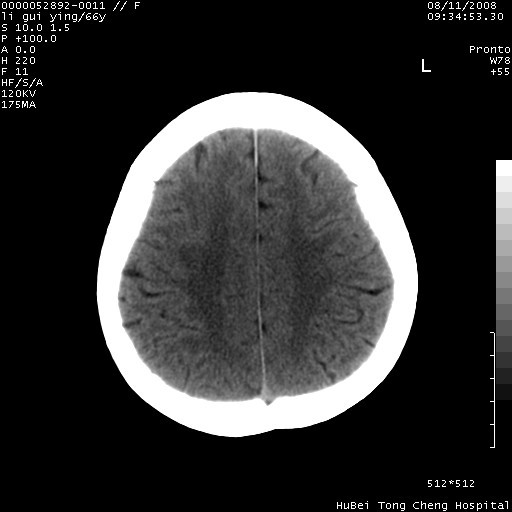

以下是引用yangyudong333在2008-8-12 12:22:00的发言:[br]1.病灶呈圆形[br]2.周围无水肿带[br]3.密度不均匀,内有点状钙化[br]4.无占位效应[br] 考虑良性占位性病变,血管瘤可能性大